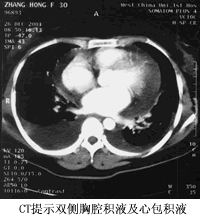

双侧胸腔积液、心包积液

患者于2001年10月底开始出现活动后心悸、气短,同时伴咳嗽,咯少量白痰。2001年11月20日在当地医院查纯蛋白衍生物(PPD)“+++”,胸部CT示双侧胸腔积液、少量心包积液,考虑为“结核性胸腔积液、心包积液”,于2001年12月1日开始抗结核治疗。20天后加用泼尼松30 mg /日及利尿剂治疗,但上述情况无明显改善。患者自起病以来无发热、盗汗、乏力、胸痛等症状,无夜间阵发性呼吸困难。胃纳好,体重无明显改变。

留永健医师(呼吸科):该例患者的基本临床特点为:青年女性,病程4个月。咳嗽、气短。双下肺叩浊,呼吸音低,双肺底细湿罗音,心界增大。胸部X线(CXR)及CT:双侧胸腔积液,心包积液,肺瘀血。痰少,无发热盗汗,血象不高。胸水为漏出液(TPP/TPB15mm的患者预后较差。治疗上应针对原发病,心脏方面可采取对症支持治疗。